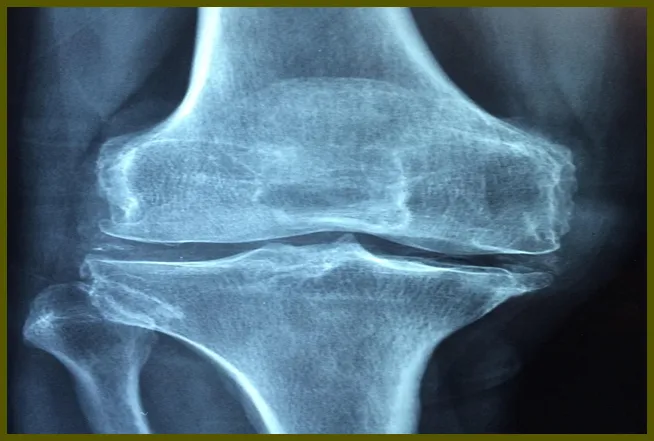

무릎연골 손상은 대개 외상이나 반복적인 스트레스로 인해 발생하는 증상입니다. 연골은 뼈와 뼈 사이에서 충격을 흡수하고 마찰을 줄이는 역할을 합니다. 그러나 이 연골이 손상되면 무릎 통증이나 불편함을 유발하게 됩니다. 이러한 증상은 일반적으로 노화, 사고, 혹은 비만 등 다양한 요인으로 인해 발생할 수 있습니다.

무릎연골 손상은 대개 두 가지 주요 유형으로 나눌 수 있습니다. 첫 번째는 단순한 마모로, 나이가 들면서 자연스럽게 발생하는 경우입니다. 두 번째는 사고나 부상으로 인한 급성 손상으로, 이 경우에는 통증과 함께 갑작스러운 움직임 제한이 동반될 수 있습니다.

무릎연골 손상이 발생할 때 나타나는 증상은 다양합니다. 일반적인 증상으로는 무릎 통증, 부기, 그리고 관절의 경직 등이 있습니다. 이러한 증상들은 개인의 상태에 따라 다르게 나타날 수 있습니다.

무릎의 통증은 연골 손상의 가장 흔한 증상입니다. 이 통증은 특정 동작을 할 때, 예를 들어 계단을 오르내릴 때 더욱 심해질 수 있습니다. 또한, 무릎을 구부릴 때 마찰음을 느끼거나, 무릎 부상 이후의 적절한 회복이 이루어지지 않았을 때 나타나는 불편함도 포함됩니다.